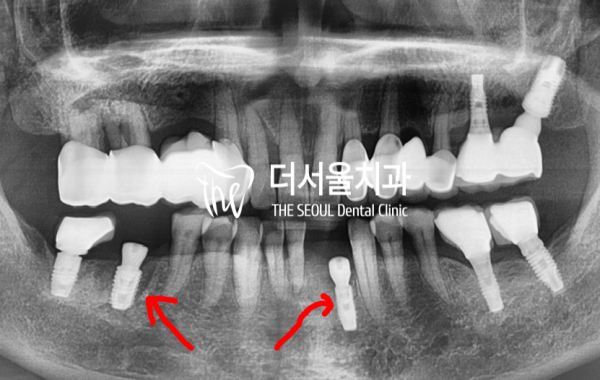

엑스레이를 통해 확인을 해 보니, 하악 앞니 뿌리주변에

염증이 있는것을 한눈에 확인할 수 있었습니다.

X-rays show that the root area of the mandible's front teeth is around the root area

I could see at a glance that there was inflammation.